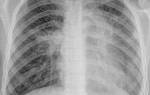

После 7-ми дней приема назначается контрольный рентген легких, с помощью которого врач оценивает состояние респираторной системы пациента и эффективность проведенного лечения.